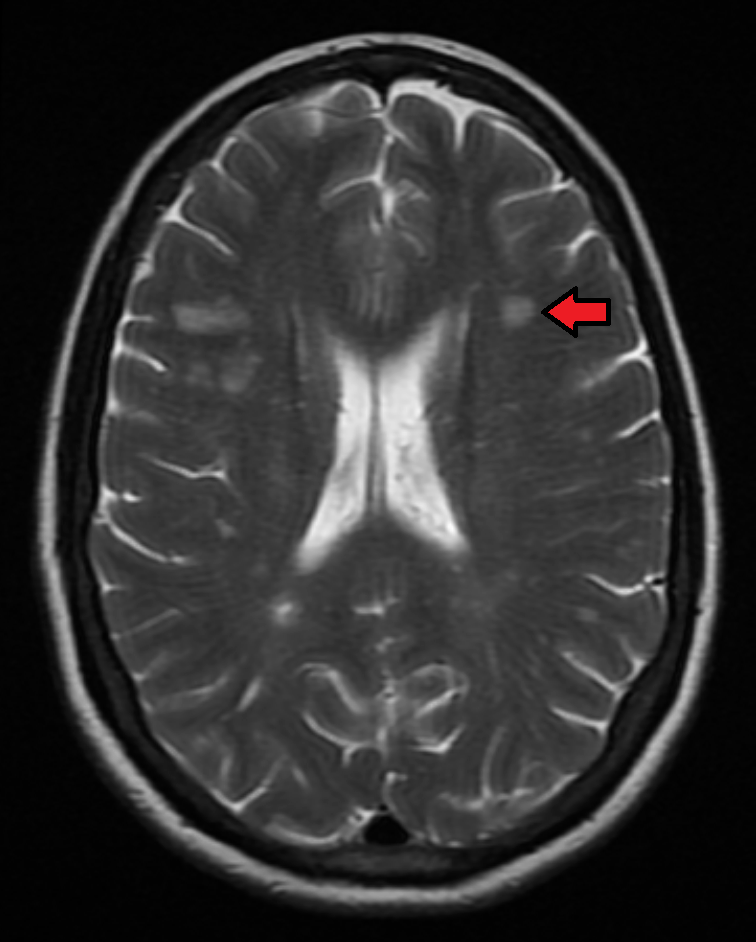

Through MRI, a contrast agent called gadolinium is used to highlight lesions with active demyelination. The McDonald criteria is the most commonly used criteria to diagnose MS, combining both clinical assessment of symptoms and the additional tests mentioned. In order to diagnose MS using this criteria, a patient must have a least one symptomatic episode, as well as an MRI scan showing lesions at various stages and locations in the CNS.

Figure 12-54. MRI showing MS lesion (red arrow) using gadolinium contrast

https://commons.wikimedia.org/wiki/File:MSMRIMark.png